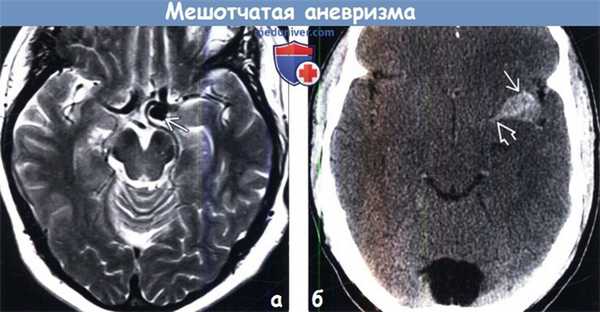

(а) Проходимые мешотчатые аневризмы визуализируются на МР-изображениях как округлые гипоинтенсивные участки потери сигнала за счет эффекта потока. Представленная мешотчатая аневризма, локализующаяся в области бифуркации ВСА, обнаружена случайно на Т2-ВИ при МРТ головного мозга пожилого пациента.

(б) КТ-ангиография, проекция максимальной интенсивности, корональный срез: у того же пациента определяется мешотчатая аневризма диаметром 4 мм, располагающаяся кверху от передней соединительной артерии.